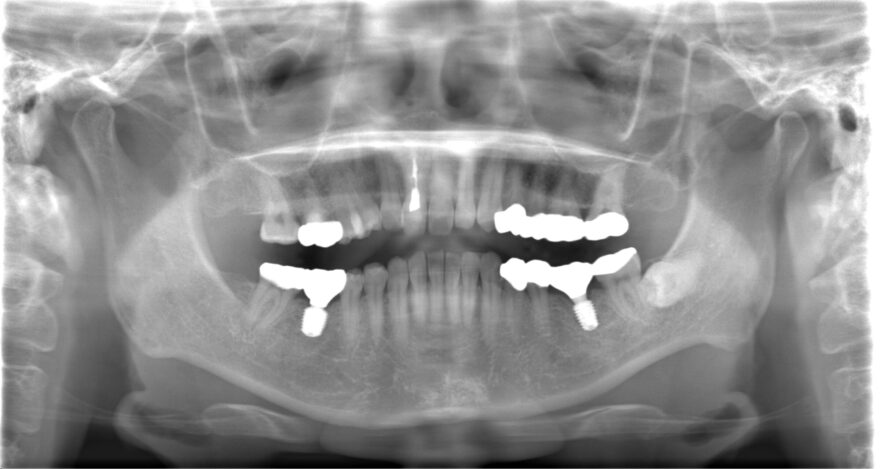

治療後のレントゲン写真

この症例の治療費

前歯プレミアムセラミック2本→330,000円(税込)

《1本あたり165,000円(税込)》

ファイバーコア1本(神経ない歯への補強材)→22,000円(税込)

奥歯インプラント2本→880,000円(税込)

《1本あたり440,000円(税込)》

奥歯用セラミック3本→330,000円(税込)

総額 1,232,000円(税込)